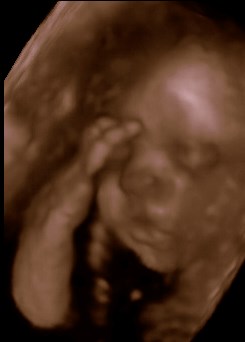

Se lige vores smukke datter

Det tog lidt tid, før hun ville vise os sit skønne ansigt, men hold da op, det var ventetiden værd!